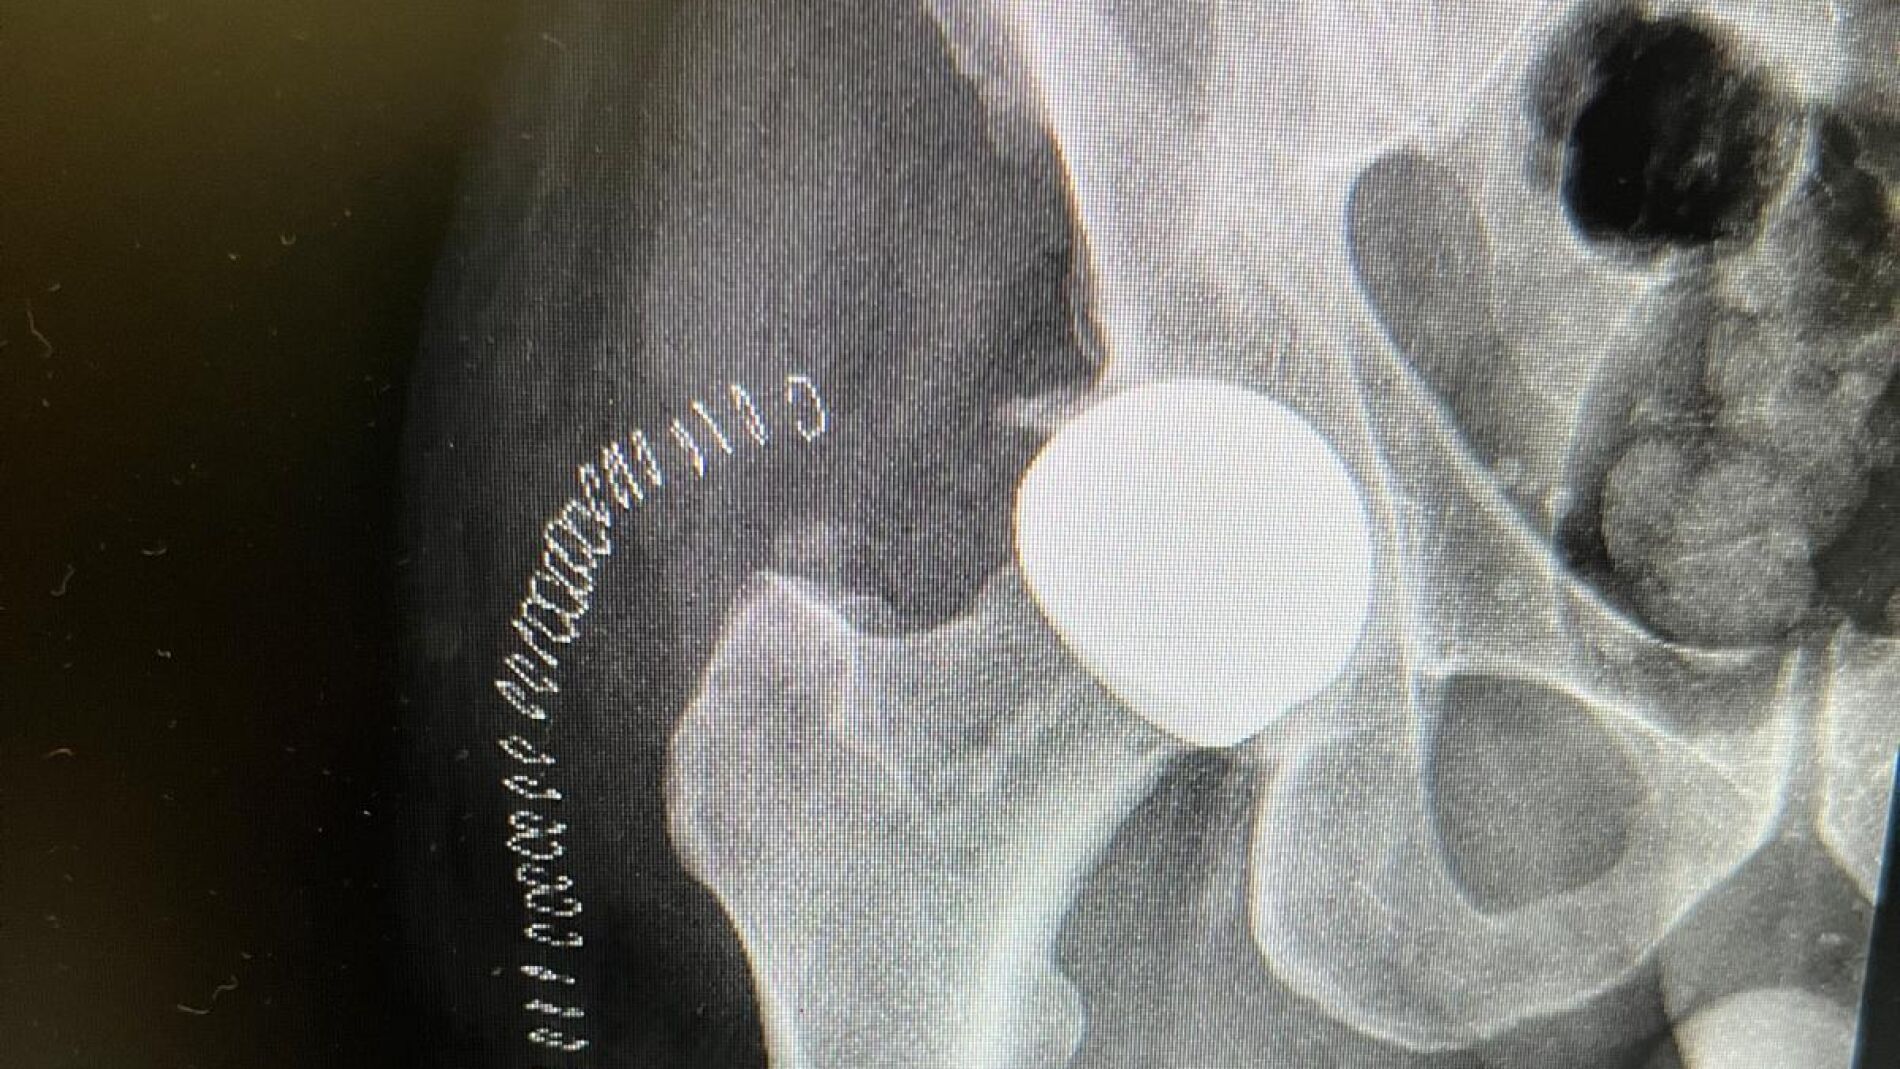

Caderas cerámicas para los pacientes más jóvenes

El Hospital Santa Cristina, de Madrid, es el primer centro público en implantar este tipo de prótesis...